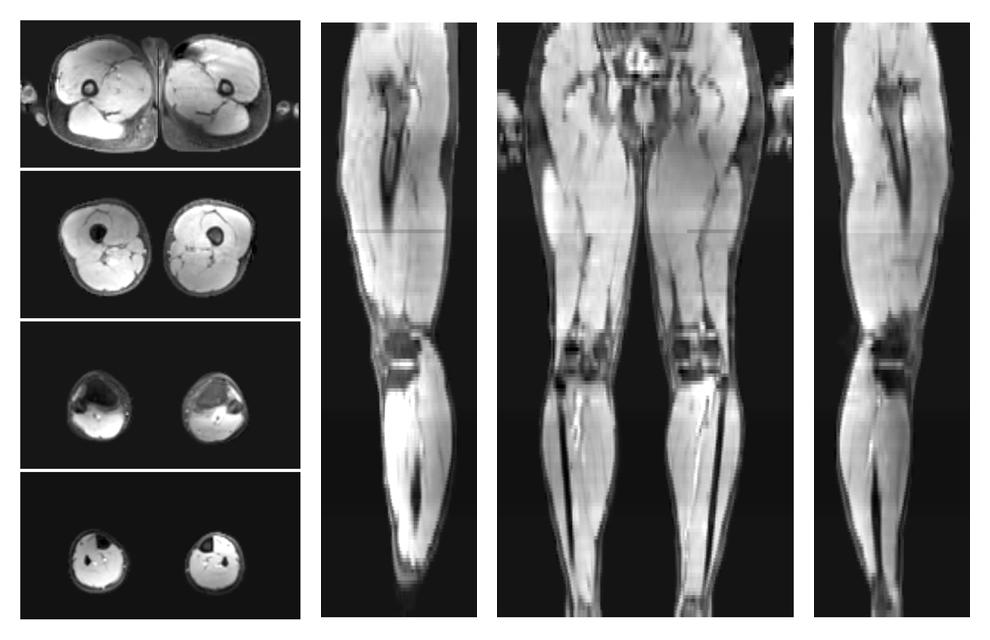

• Water only signal

The water part of the acquired multi-echo spin echo data.